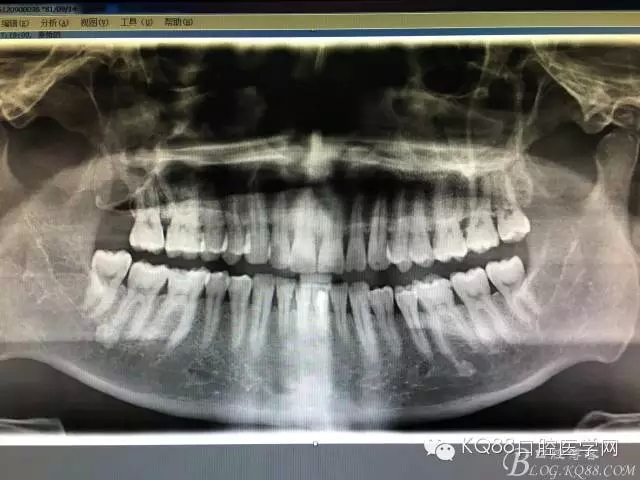

圖2.術前做全景片影像檢查:18頰舌向高位阻生,牙冠位于17牙根的正上方,懷疑18位于上頜竇內(nèi)。

圖3.加拍CBCT影像檢查:18位于上頜竇內(nèi),并導致右側上頜竇粘膜炎性增生。18牙冠的合面朝向頰側。并且與17頰根緊密相鄰。